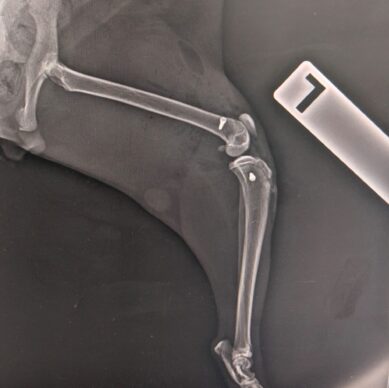

Kedi